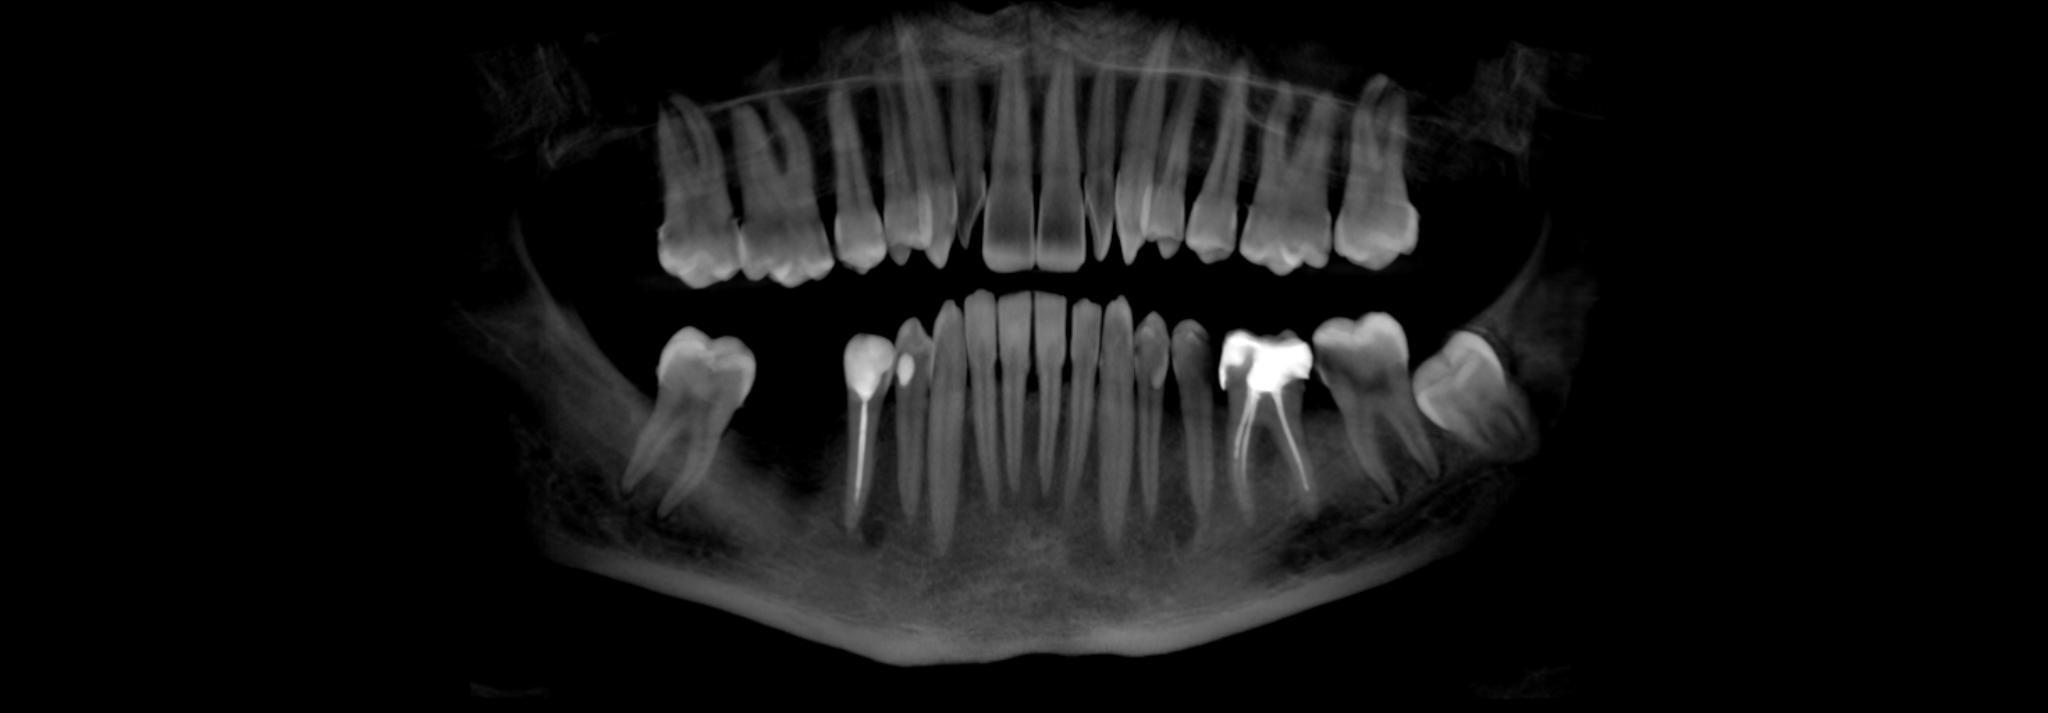

Дабы не перегружать вас обилием одинаковых картинок, я оставлю один рентгеновский снимок, но отмечу, что установка имплантатов на верхней и нижней челюсти проводилась с разницей в 10 дней.

На верхней челюсти было дополнительно удалено два боковых резца с одномоментной установкой имплантатов, так же они были установлены в области четверок и шестых зубов. Дополнительно было проведено наращивание костной ткани - двусторонний синус - лифтинг. О том, что это такое, можно почитать ТУТ и ТУТ.

Контрольный рентгеновский снимок:

Вот так было:

А как стало на промежуточном этапе: